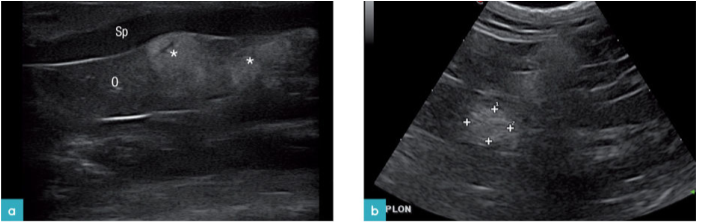

若腹腔有遗留的纱布块或霉菌病会演变成肉芽肿和脓性肉芽肿。而纱布块会产生声影(图21.视频2)。

一例真菌聚集型肉芽肿产生高回声病灶伴回声衰减,容易被误认为钙化灶。异物容易引发肉芽肿反应,例如草芒或小枝(图22)。

结节性脂肪坏死在肥胖的猫较多见。它是边缘清晰的,高回声并发生有衰减的肿块(实质发生钙化),中心为低回声(图23.视频3)。